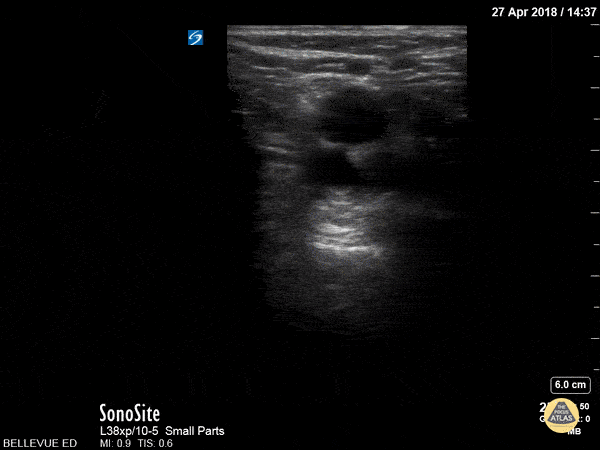

76 y/o M with DOE, no hx of CHF, no signs of infection, smoking hx. What is the finding AND Likely diagnosis after seeing this scan of the Left lung base:

Septated pleural effusion likely exudative, Suspected malignancy